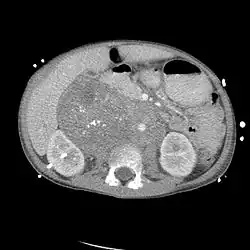

Das Neuroblastom ist mit sieben bis acht Prozent aller Krebserkrankungen im Kindesalter die dritthäufigste bösartige Neubildung bei Kindern. Vom autonomen Nervengewebe – der embryonalen Neuralleiste – ausgehend handelt es sich um einen Tumor, dessen Zellen (sogenannte Neuroblasten) in einem unreifen Stadium verblieben sind. Er ist vor allem in den Nebennieren, entlang der Wirbelsäule, im Kopf-, Hals- und Nackenbereich sowie im Brust-, Bauch- und Beckenraum entlang des zervikalen, thorakalen und abdominalen Grenzstranges sowie in den Paraganglien anzutreffen. Circa 70 Prozent liegen außerhalb des Bauchraumes im Retroperitonealraum und etwa 20 Prozent zwischen den Lungenflügeln im Mediastinum.

Die Diagnose erfolgt in den Frühstadien meist zufällig mittels Ultraschall, Computertomografie (CT) oder Magnetresonanztomografie (MRT), die aus anderen Anlässen angefertigt wurden. In der Folge führt die MIBG-Szintigraphie zur Lokalisierung des Primärtumors und der eventuell schon vorhandenen Metastasen. Die Skelett-Szintigraphie mittels Technetium-Phosphonaten wird zur Unterscheidung zwischen Knochenmarks- und Knochenmetastasen herangezogen. Die histologische Abgrenzung von Neuroblastomen zu anderen Tumorgruppen sowie die Einschätzung ihrer biologischen Dignität erfolgen üblicherweise auf Grundlage der international anerkannten International Neuroblastoma Pathology Classification (INPC). Ergänzend zur morphologischen Klassifikation hat sich die genetische Analyse des Tumorgewebes als ein wertvolles Instrument zur präziseren Einschätzung der Aggressivität des Tumors (Dignität) etabliert. Auf Basis einer großen Zahl molekulargenetisch gut charakterisierter Neuroblastome konnte in internationalen Studien eine differenziertere Risikostratifizierung entwickelt werden, die genetische Merkmale der Tumorzellen berücksichtigt. Die Kombination aus klinischen Daten, bildgebenden Verfahren, morphologischen Befunden und genetischen Profilen bildet die Grundlage für ein personalisiertes therapeutisches Vorgehen, wie es unter anderem im Rahmen der International Neuroblastoma Risk Group (INRG) und der INRG-Biologie-Initiative publiziert wurde.[1][2]